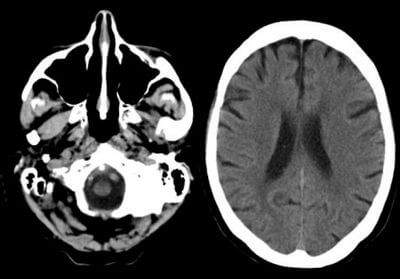

КТ, також відома як комп'ютерна томографія, є важливим інструментом медичної візуалізації, який дозволяє лікарям зазирнути всередину організму. Технологія, що використовується в КТ, створює детальні зображення тіла’КТ дозволяє отримати зображення внутрішніх структур організму, що робить її безцінним інструментом для діагностики та моніторингу стану здоров'я. Однак, як і будь-яка медична процедура, існують обмеження та протипоказання, які слід враховувати перед проходженням КТ.